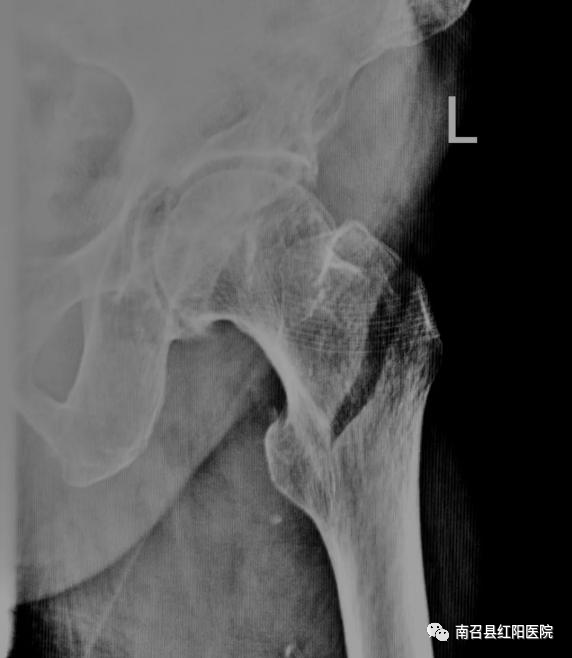

年轻人骨骼肌肉结实,除非是十分巨大的暴力作用,一般摔倒并不容易发生骨折。老年人,骨质开始变得疏松,肌肉萎缩,特别是绝经后妇女,骨质丢失更加严重。这时候髋部非常脆弱。一旦发生摔倒、滑倒,身体扭转倒地,就很容易造成髋部骨折。老年人髋部骨折后翻身和坐起疼痛不便,一般髋部骨折保守牵引治疗通常要 2~3 个月甚至更长,一旦长期卧床,就很容易造成呼吸系统感染、泌尿系统感染、深静脉血栓和褥疮等并发症,生活质量更低,进而危及生命。传统认为老年人骨折最好保守治疗,部分家属会说:“年纪大了,不再冒险受罪,不考虑手术了”,或者是担忧能否能耐受手术风险。事实上,随着医疗技术,特别是麻醉进术的快速提高,老年髋部骨折绝对禁忌症非常少。术前多学科联盟细致全面准备,使得许多百岁老人受益于外科治疗而快速恢复。目前对于股骨颈骨折一般采取人工关节置换术,对于粗隆间骨折多采用髓内钉内固定,部分患者也可以采用人工髋关节置换术,两种手术都很成熟。手术时间可控制在一个小时之内,出血量很少,绝大多数老人都可以耐受。术后一周内患者可以部分负重下床活动,避免卧床护理压力及卧床并发症。近日我院收治多例髋关节骨折病人,大部分为高龄、合并基础病较多,其中一老年女性,96岁,高龄,股骨转子间骨折,心肺功能较差,手术风险高,但患者家中困难,只有一个儿子在身边照顾,且儿子已经70余岁高龄,本身身体不好,家属为求后期方便照顾、减轻家庭负担遂要求手术治疗,积极术前检查,充分评估患者心肺功能,术前请麻醉科、代主任、王院长会诊,将手术及麻醉风险降至最低,充分评估病情后行股骨转子间骨折切开髓内钉内固定术,麻醉及手术顺利,患者术后恢复良好,现患者可坐立、屈膝屈髋及自己翻身,术后活动明显改善。